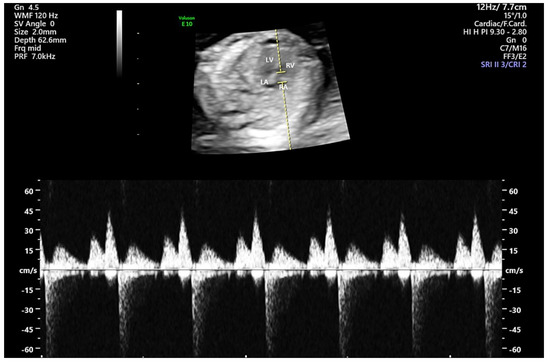

| TR velocity (cm/s) | 11.5 ± 5.3 | 30.1 ± 10.8 | <0.001 |

| Tricuspid E wave velocity (cm/s) | 24.1 ± 6.0 | 29.1 ± 8.3 | <0.001 |

| Tricuspid A wave velocity (cm/s) | 45.5 ± 8.8 | 53.2 ± 12.8 | <0.001 |

| Tricuspid E/A | 0.5 ± 0.1 | 0.5 ± 0.1 | 0.029 |